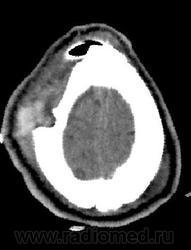

Обратите внимание на субдуральное пространство справа. Определяется тонкое пластинчатое скопление патологического изоденсного содержимого над конвекситальными отделми правой гемисферы большого мозга. Слева оболочечные пространства выражены обычно.

Каюсь, я так сосредоточилась на костных изменениях, что факт наличия этого содержимого в третьем часу ночи был мной упущен.

Была произведена фронтотомия, эвакуировано гнойное содержимое. Пациент в сознании, актвен, был госпитализирован в ЛОР-отделение. Через 3 дня клиническое ухудшение состояния, сопор. Выполнено контрольное КТ головного мозга с контрастным усилением.

-над лобной, височной и теменной долями правого полушария большого мозга определяется скопление патологического содержимого плотностью до +20HU, размерами 122х14х98мм(V~87см3)- субдуральная эмпиема, размеры ранее описываемого участка гиподенсной плотности в полюсно-базальных отделах правой лобной доли (+25+30Hu), увеличились до 36х11мм. Смещение срединных структур влево до 10мм.